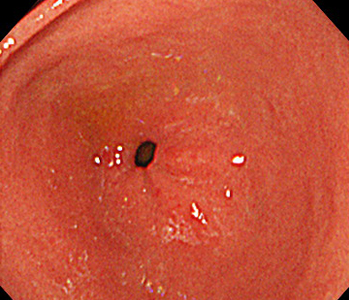

胃内視鏡(胃カメラ)画像

| ◆ 経口内視鏡(高解像度)◆ | ◆ 経鼻内視鏡 ◆ |

| 幽門 | 幽門(経鼻) |